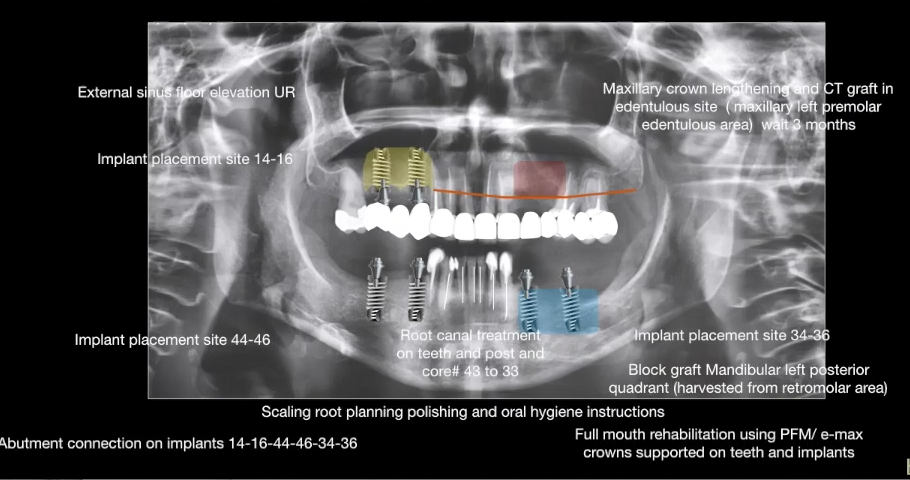

The management of the anterior open bite may be quite challenging and in some cases necessitates a multidisciplinary approach. We present here a patient suffering from an anterior open bite with an ankylosed central incisor due to previous trauma. The anterior open bite was corrected using conventional orthodontics and the ankylosed incisor was repositioned in the correct tri dimensional position using segmental osteotomy. The repositioned bone block needed 5 months of stabilization and the prosthetic rehabilitation of the anterior maxilla was completed using e-max crowns. At 24 months ,the result was stable with no relapse and an excellent pink and white esthetic score.